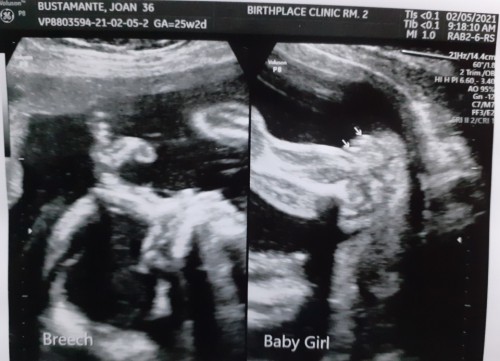

6 mos.preggy breech position

hi mga momsh.. any suggestion or advice? breech position si baby 6 mos. in my tummy. ndi na ganu nag sink in sa kin mga sinabi ng OB during UTS😁 nacarried away kasi at na excite nung sinabi nia agad na girl baby ko...

Iikot pa daw si baby kapag ganun, sakin kasi ganun din but nung bago manganak nakapositionnna si baby naka-normal delivery pa ako :)